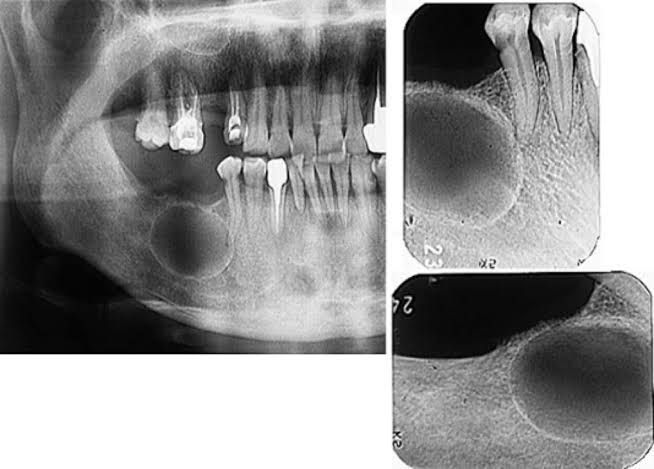

Odontogenic keratocysts (OKCs), first described by Philipsen in 1956 [1], are benign intraosseous lesions of odontogenic origin that account for about 10% of jaw cysts. They are characterised by an aggressive behaviour with a relatively high recurrence rate Odontogenic keratocysts (OKCs) are generally thought to be derived from remnants of the dental lamina (rests of Seres), traumatic implantation or down growth of the basal cell layer of the surface epithelium, or reduced enamel epithelium of the dental follicle